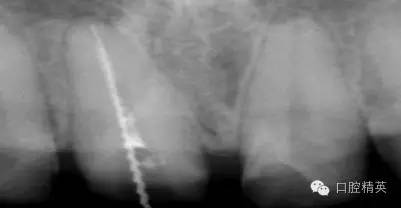

根管治療更是牙體修復(fù)的基礎(chǔ),根據(jù)術(shù)前診斷,對需要做根管治療的或有必要重新做根管治療的,一定要做到恰充,消除隱患,避免將來冠修復(fù)好后,出現(xiàn)根尖炎癥的問題(見圖3、4、5)。在基礎(chǔ)工作做好后,接下來開始牙體預(yù)備,根據(jù)跟個(gè)人習(xí)慣,選擇合適的車針(圖6、7)。